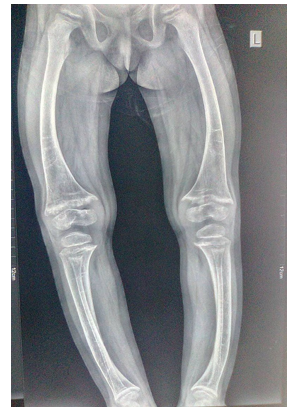

Old radiographs of the younger sister showed osteopenia, fracture in the upper limb, and progressive bowing with no rachitic changes. Figure-3A and 3B show lower limb radiographs showing progressive bowing. Figure-4 (A, B, C, and D) show recent bone radiographs of the younger sister taken during May, 2023 which showed osteopenia, bowing with no rachitic changes. Radiograph of the pelvis showed mild protrusio acetabula (Figure-4A). Radiograph of the wrist showed no rachitic changes (Figure-4B). Radiograph of the lower limbs showed bowing, cortical thinning with scanty spongiosa (Figure- 4C). Lateral skull radiographs showed platybasia (Figure-4D).

Figure-4A: Radiograph of the pelvis showing mild protrusio acetabula

Figure-4B: Radiograph of the wrist showing no rachitic changes

Figure-4C: Radiograph of the lower limbs showing bowing, cortical thinning with scanty spongiosa

Figure-4D: Lateral skull radiographs showed platybasia